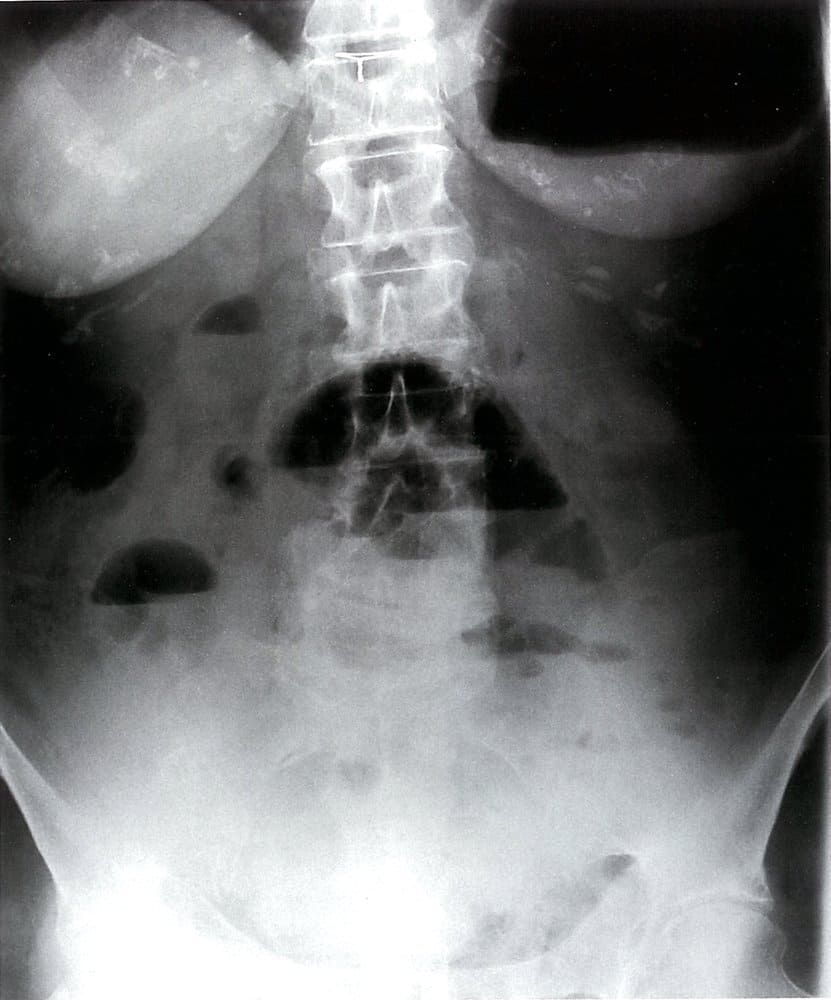

انسداد روده

انسداد روده به قطع جریان طبیعی محتوای روده گفته میشود که میتواند به دلیل انسداد عملکردی یا مکانیکی باشد. انسداد عملکردی روده یا ایلئوس پارالیتیک، یک اختلال موقتی در حرکات دودی روده در غیاب انسداد مکانیکی است (نگاه کنید به “ایلئوس فلجکننده”). انسداد مکانیکی روده به منزله قطع شدن جریان طبیعی روده به دلیل وجود مانع ساختاری است. انسداد مکانیکی روده را میتوان با توجه به محل آن به دو گروه انسداد روده باریک (SBO) یا انسداد روده بزرگ (LBO) طبقه بندی کرد یا براساس میزان انسداد،به پارشیل یا کامل طبقه بندی کرد.